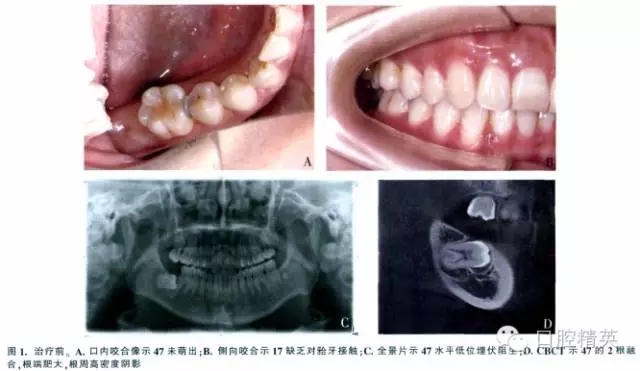

女,37歲,右下頜埋伏牙,要求治療。檢查示面型對稱,側(cè)貌正常。47未萌,17腭尖下垂,其余牙咬合好(圖1A、B)。全景片示:47水平低位埋伏,47冠方有一不完整的透明陰影,周圍呈現(xiàn)白色反應(yīng)線,根方有致密陰影(圖1C)。錐形束CT(CBCT)示47接近水平位,牙長軸與牙合平面前上方夾角約為75°,根尖端肥大,牙周膜間隙模糊(圖1D)。